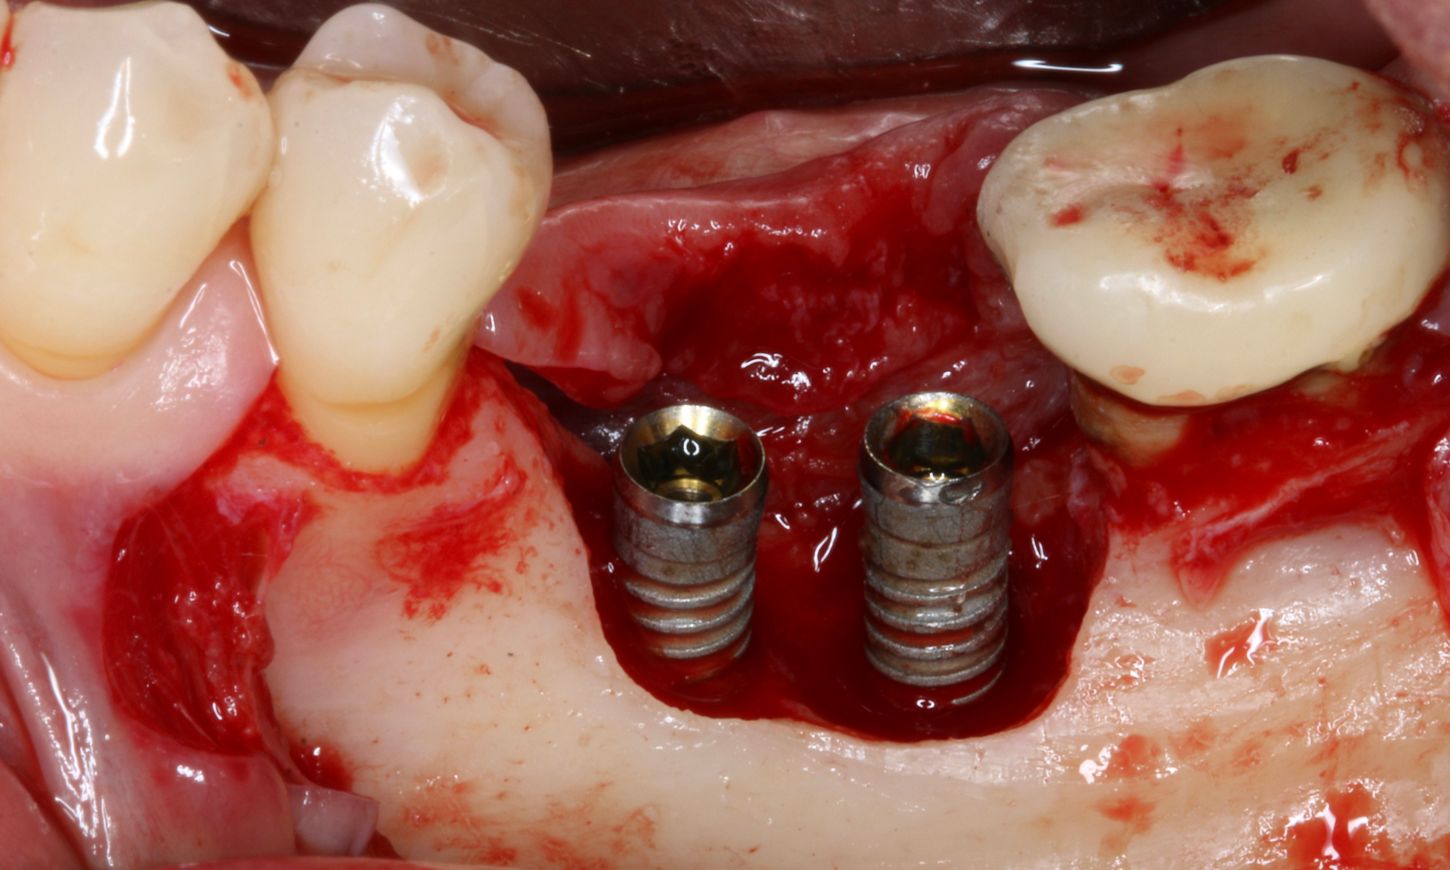

A full-thickness flap was elevated to access the defect and mechanically remove the granulation tissue surrounding the implants (Fig. 4). The bone defect was assessed using the modified criteria established by Monje et al, and was classified as a Class 3b defect, making it suitable for reconstructive therapy. First, implant disinfection was done with ablative mechanical debridement, CHX 0.12 %, metronidazole 5mg/ml, and a solution of local antibiotic and hyaluronic acid (Fig. 5).

Fig. 4

Fig. 5